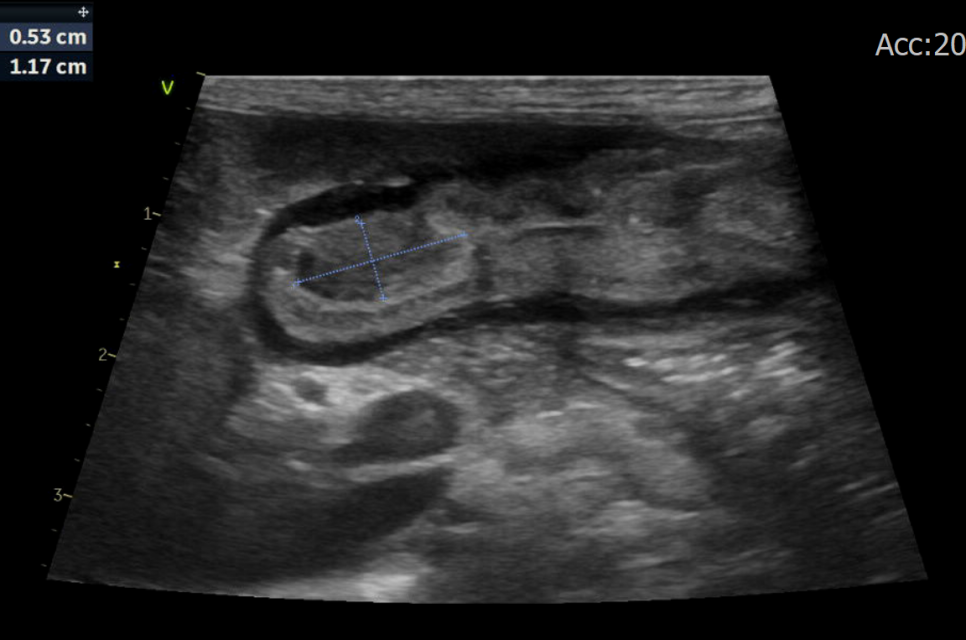

복부 초음파에서 위 유문부 병변이 관찰

▶ 복부 초음파 검사 소견

복부 초음파 검사 결과, 위 유문부 부위에서 종괴 형태의 병변이 관찰되었습니다.

병변은 내강 쪽으로 돌출된 형태였으며, 위 배출을 부분적으로 방해할 가능성이 있어 보였습니다.

이러한 소견을 종합했을 때 위 유문부 폴립(polyp) 이 의심되었고, 확진 및 치료를 위해 내시경 검사를 계획하였습니다.